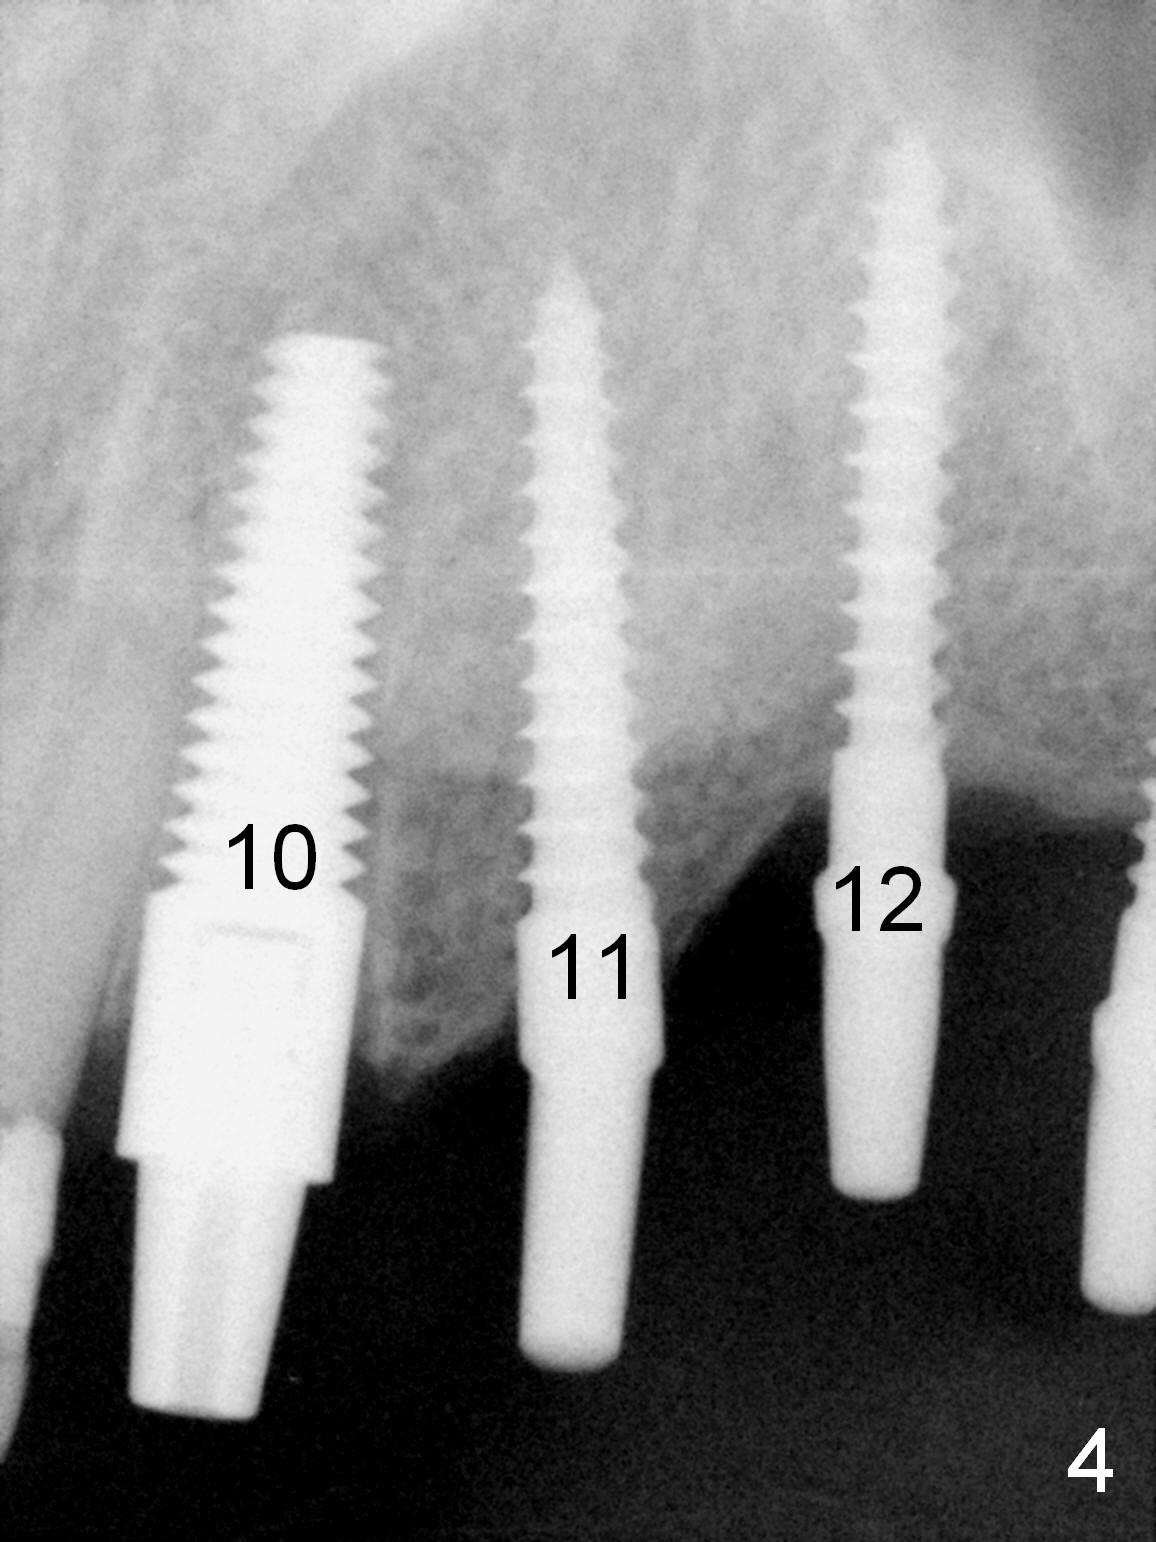

When the patient returns for implant placement (2nd visit after initial exam), he reveals that he is a dental phobic. He requests placement of 4 implants in the upper left quadrant, instead of 2. Narrow ridge is unexpected in the canine and premolar area (Fig.1). Limited bone height at #13 (Fig.3 arrowheads: sinus floor) is found when initial drills are in place (Fig.2,3). A 2-piece implant (4.5x17 mm tissue-level) is placed at #10 after extraction, while 1-piece implants are placed at 11 (3x17 mm (tissue-level, 15 °) and 12 and 13 (bone-level, 2.5x14, 12 mm, respectively; Fig.4,5). In fact the 1 piece implant at #13 is not completely placed (Fig.5). It is removed, the apical 3 threads are cut off (Fig.6 <, since a shorter implant was unavailable in the office) and the remaining implant is re-inserted. The insertion torques of the 4 implants are ~ 60, ~ 35, < 35 and 15 Ncm, respectively. After adjustment (Fig.7), immediate provisionals are fabricated at #10 and 11 (Fig.8, later splinted with composite), while perio dressing is applied around the implants at #12 and 13 and the provisionals at #10 and 11. There is no nasal hemorrhage postop. Although the perio dressing is loose 1 week postop (Fig.9), it is not removed. When the upper lip fissure (Fig.9 <) heals, provisionals at #12 and 13 are planned to be splinted to the other two ones. Two weeks postop, the upper lip fissure heals, the perio dressing dislodges and the implants at #12 and 13 are stable (Fig.10). After abutment height adjustment, a splinted provisional is fabricated over these 2.5 mm 1-piece implants (Fig.11).